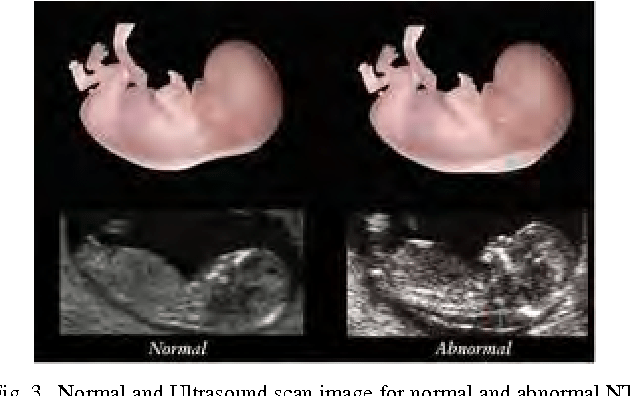

The Ultrasound Marker Is The Thickness Of The Core Transparency (Nt).

Down syndrome is one of the most common genetic birth defects. Lack of a nasal bone, dilation in the kidneys, and bowel or heart defects can all be signs that down syndrome may be present. Thickened nuchal fold ( nuchal translucency) duodenal atresia (double bubble) echogenic bowel.